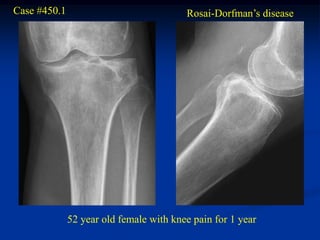

Sinus histiocytosis is a rare and new variant of the histiocytoses

which is characterized by enlarged lymph nodes in the head and

neck area in 80% of cases along with bony involvement in 40%

of cases. It is an aggressive form of the histiocytoses that is seen in

teen agers and young adults. Symptoms may include fever, weight

loss and malaise. The bony lesions may be solitary or multifocal

and suggest inflammatory disease such as chronic osteomyelitis or

EG. The pathology shows mononuclear or multinuclear giant cells

with lymphs in the cytoplasm of the giant cells. Other inflammatory

cells such as plasma cells, lymphocytes and foamy histiocytes may

be seen. 10% of those with bone lesions die of the disease from extra-

skeletal involvement of the lungs and kidneys.

Case #450.1                              Rosai-Dorfman’s disease

52 year old female with knee pain for 1 year

Sag T-1         T-2

Gad

Axial T-1   T-2

Cor T-1         T-2

Post op X-ray